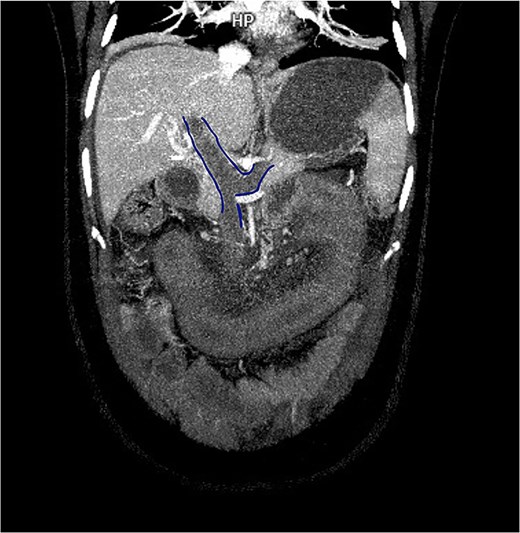

Contrast-enhanced computed tomography (CT) demonstrated thrombosis of the portal vein, splenic vein, and superior mesenteric vein with proximal dilatation, diffuse jejunal thickening, mesenteric fat stranding, and mild splenomegaly (Figs 1 and 2). No pneumatosis or portal venous gas was seen.

3D contrast-enhanced CT rendering reconstruction in venous phase showing thrombosis of the portal, splenic, and superior mesenteric veins with proximal dilatation and thickening of the jejunal wall.